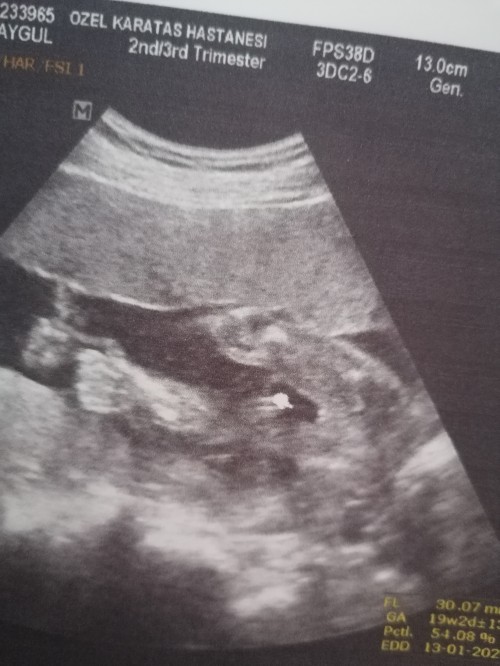

Kızlar 12. Haftada doktorum erkek dedi. 19.haftada başka doktor kız dedi. Anlayan varsa yazabilir mi? Benm ilk gebeliği, bilemiyorum ben.

Bence kız.Evet işaretlediğin yerde parlak bir yuvarlaklık var ama bacakların birleşim yerinin çok altında boşta duruyor gibi.Bacakların birleştiği yerde kız organı bence çok belli.